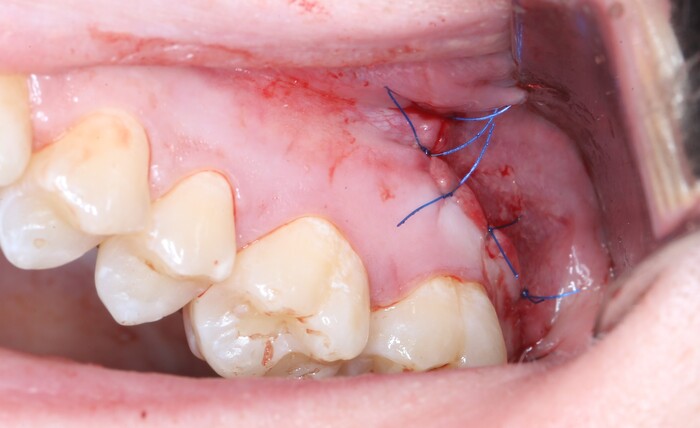

Далее швы и в общем-то и все: